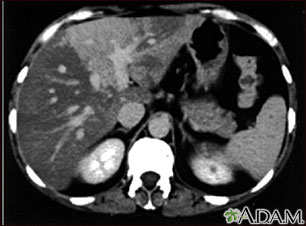

Esta es una TC del abdomen superior que muestra esteatosis desproporcionada del hígado (hígado graso).